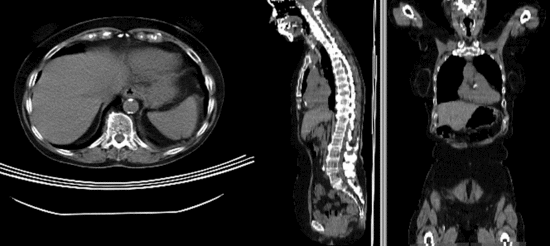

• Phase II: Preprocessing: crop

1. Crop to region of interest: to avoid bias from the strong differences in head positiion, we reduce the effective FOV do the abdominal region of interest

3. We clip both s1_CT and s2_CT between the 5th lumbar and the 5th thoracic vertebrae. For a separate tutorial on how to use the Subvolume module, see the slicer training compendium